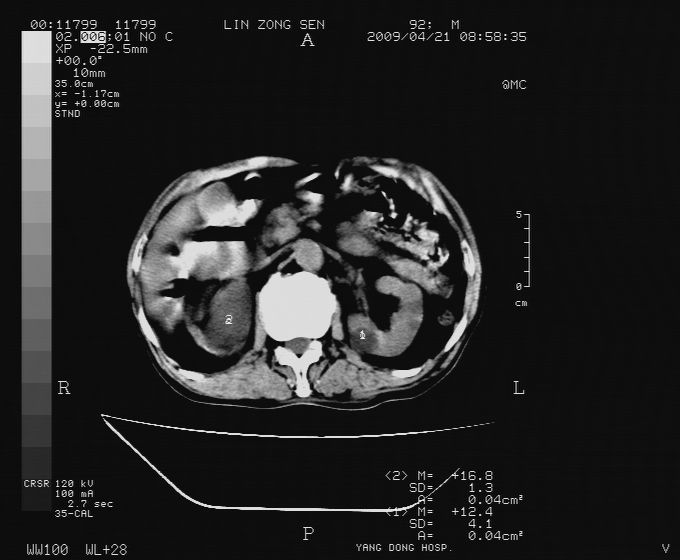

以下是引用卜一在2009-4-22 4:08:00的发言:[br]右肾积水伴输尿管上段积水!左侧肾多发囊肿!左侧腹壁软组织增厚,层次模糊,内密度较高—不排除血管瘤伴出血!